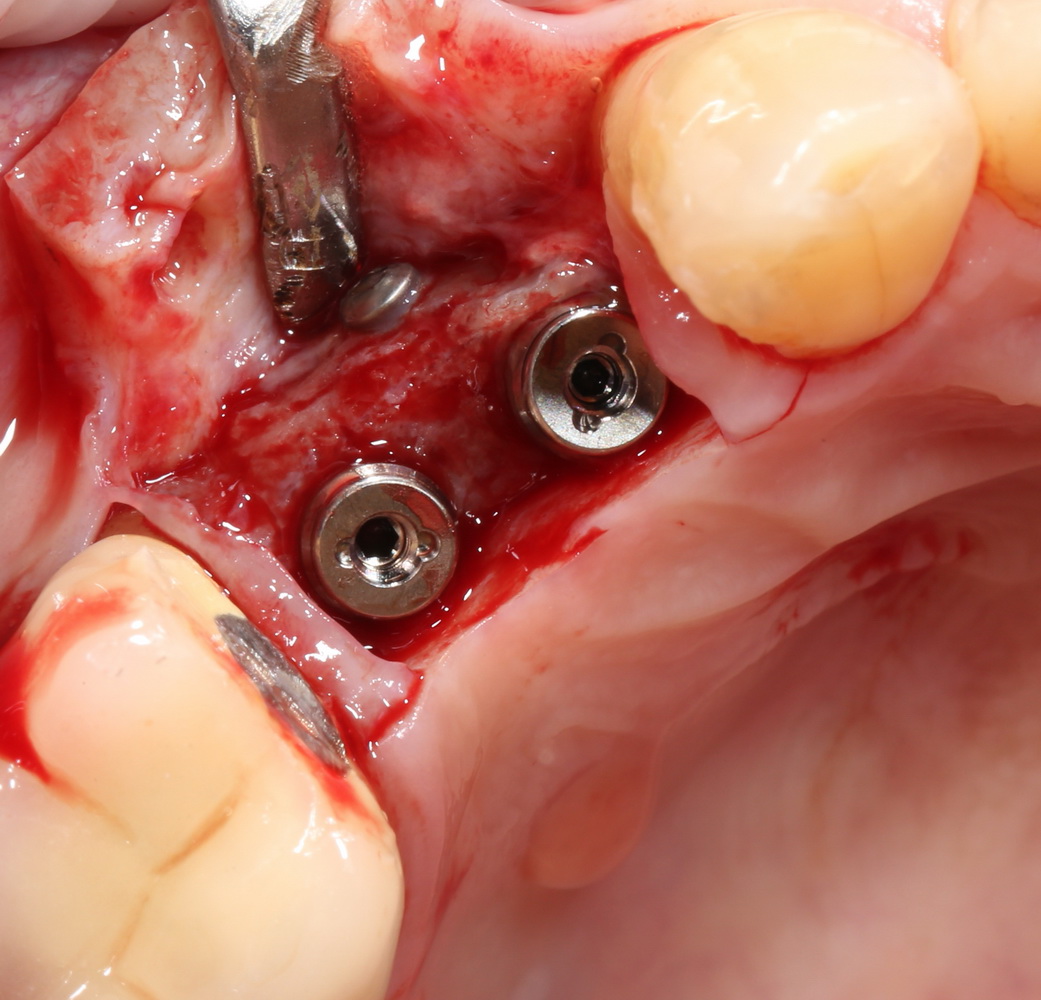

Затем устанавливаем имплантат. В данном случае, Friadent XiVE. Диаметром 3,4 мм — это минимальный размер импланта, который можно использовать в эстетически значимой зоне:

Не обращаем внимания ни на стабильность импланта, ни на объемы окружающей костной ткани. Имплантат после установки может крутиться, шататься и вращаться — правило, когда первичная стабильность была главным условием успешной имплантации, применимо лишь ко второму этапу развития имплантологии. Более того, друзья, есть импланты, которые вообще не предполагают первичной стабильности. Например, Bicon.

Очень хочется использовать имплантат поменьше диаметром (3.0 мм), но, как я уже отметил, минимальный размер в эстетически значимой зоне — 3,4 мм. Связано это с тем, что на импланты диаметром 3.0 мм выпускается очень небольшое количество супраструктур (абатментов), поэтому в дальнейшем можно столкнуться со сложностями при протезировании.

После установки второго импланта в правильное положение (ориентируемся по оси и форме лунки зуба), внешнюю кортикальную стенку восстанавливаем костным фрагментом, получившимся после синуслифтинга: